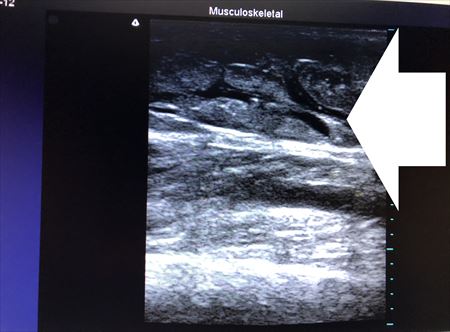

同様に他の部位も見てみましょう。 ↓ ↓ ↓

筋肉質で硬いふくらはぎ。

自力で痩せるのは難しい部位ですから

今回の脂肪吸引で可能な限り

皮下脂肪は根こそいでおきました。